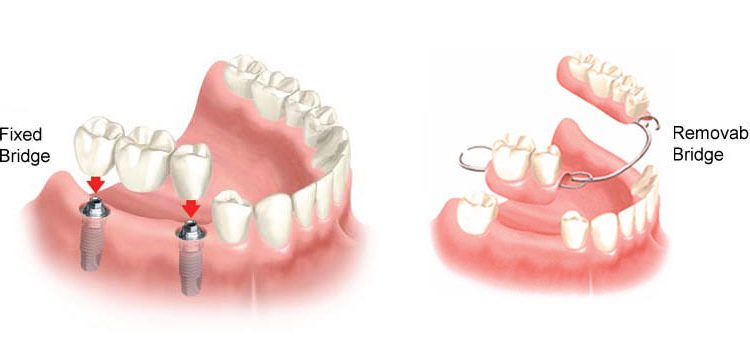

Gigi Palsu

Gigi Palsu, Crown Gigi, Implan atau Gigi Tiruan merupakan layanan Global Estetik Dental Care untuk mengembalikan fungsi gigi dalam kehidupan seperti untuk berbicara lebih nyaman dan makan lebih nyaman. Terdapat Gigi Palsu Lepasan hingga Gigi Palsu Permanen sesuai dengan keinginan anda

[3] Opsi untuk Mengganti Gigi yang Hilang, Pilih Implan, Gigi Palsu atau Bridges ?

Global Estetik - Mengapa kita perlu mengganti gigi yang hilang? Wajah manusia dirancang dengan gigi dalam skemanya. Gigi membantu menjaga struktur...

[2] Opsi untuk Mengganti Gigi yang Hilang, Pilih Implan, Gigi Palsu atau Bridges ?

Global Estetik - Mengapa kita perlu mengganti gigi yang hilang? Wajah manusia dirancang dengan gigi dalam skemanya. Gigi membantu menjaga struktur...